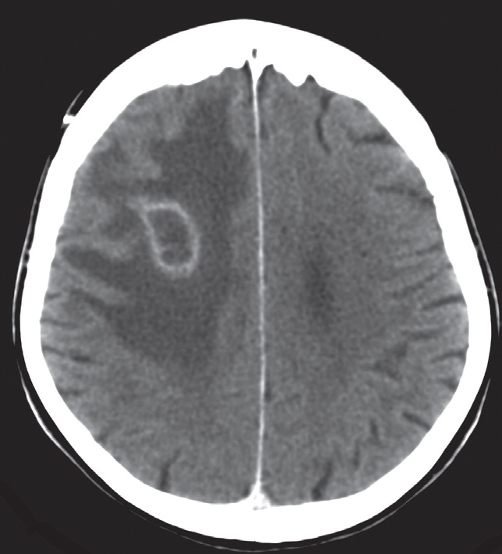

Pus in the center of the abscess appears as low density on CT or fluid on MRI. The wall of the abscess enhances with intravenous contrast and may be surrounded by oedema, giving an appearance known as ‘ring enhancement’

Cerebral abscess.

Post contrast CT scan showing a right frontal ring-enhancing lesion with surrounding vasogenic oedema